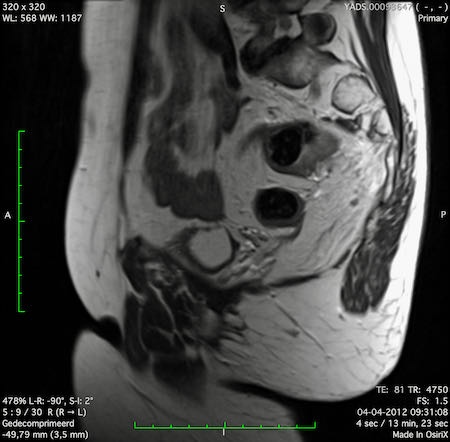

Hình ảnh

Các hình ảnh được cung cấp cho thấy ung thư biểu mô tế bào nhẫn với tình trạng dày lan tỏa thành trực tràng, hình ảnh bia bắn điển hình, và sự xâm lấn mỡ mạc treo trực tràng.